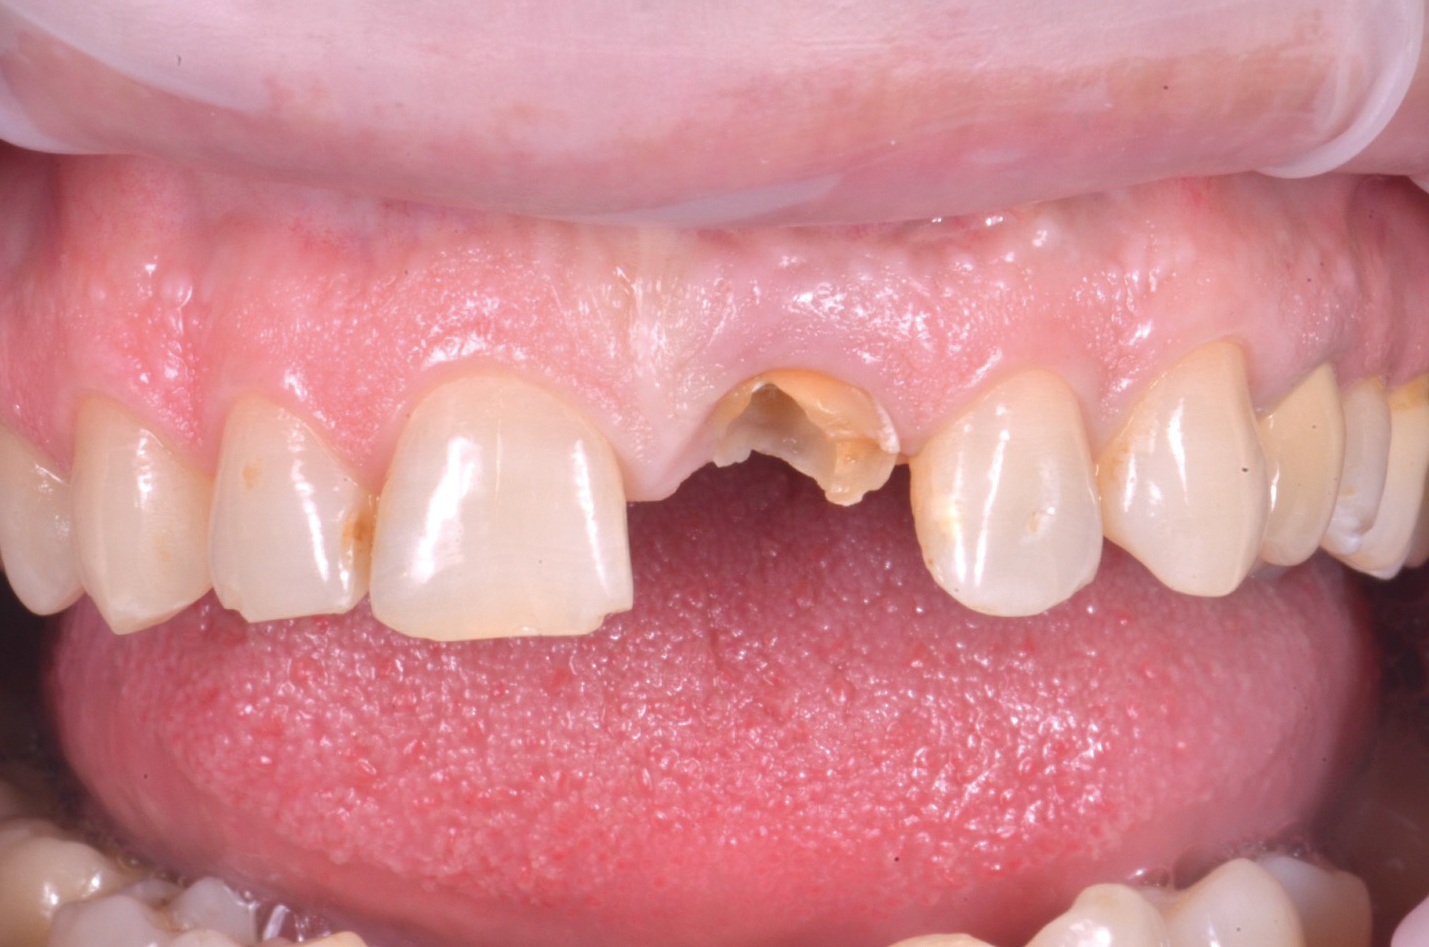

Il paziente, uomo di 50 anni, si presenta con una frattura orizzontale della corona dell’elemento 21 che lo rende non recuperabile (fig.1). Il piano di trattamento scelto è stato la riabilitazione del sito con un impianto post-estrattivo a carico immediato. Si è proceduto con la raccolta dati iniziale con scansione CBCT e impronta ottica. I dati ottenuti dalla CBCT e il file ottenuto dallo scanner sono stati importati all’interno di un software per la progettazione guidata (Msoft, MIS Implants ltd global, Bar Lev, Israele). Un terzo file corrispondente alla ceratura diagnostica ideale è stato ricavato da un software di disegno CAD (Exocad, Exocad Gmbh, Darmstadt, Germania). Una volta ottenuti tutti i file all’interno dello stesso ambiente virtuale, è stata eseguita la procedura di accoppiamento dei file e la progettazione del posizionamento implantare ideale a seconda della disponibilità ossea e dei tessuti molli come anche del futuro profilo di emergenza protesico (fig.2).